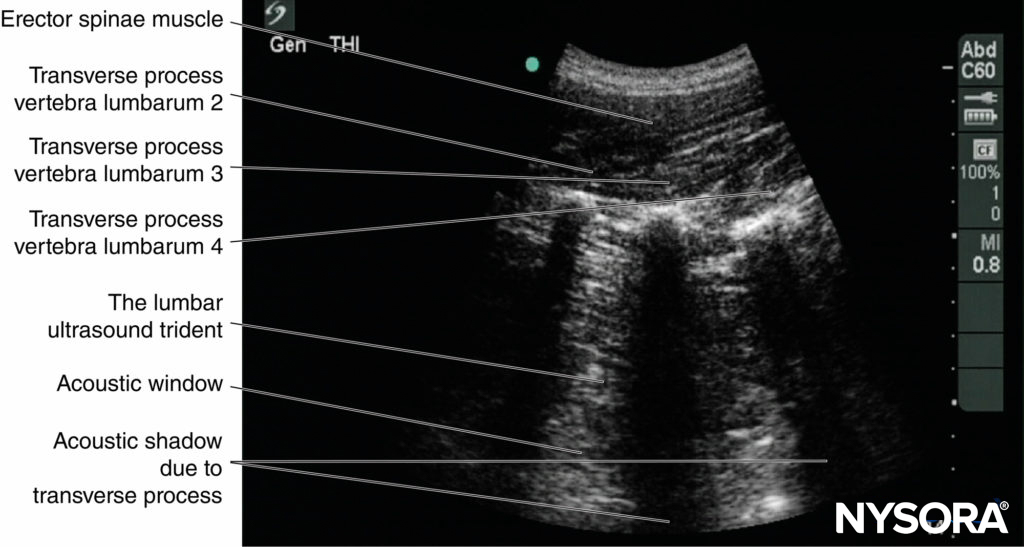

On a typical PMTOS-TP (see Figure 10b), the erector spinae muscle, transverse process, psoas major muscle, quadratus lumborum muscle, and anterolateral surface of the vertebral body are clearly visualized (see Figure 13).

The psoas muscle appears hypoechoic, but multiple areas of hyperechogenicity are also interspersed within the central part of the muscle (see Figure 13). These hyperechoic speckles represent the intramuscular tendon fibers of the psoas muscle and are more pronounced below the level of the iliac crest.

The inferior vena cava (IVC; on the right side) and the aorta (on the left side) are also identified anterior to the vertebral body (see Figure 13) and are useful landmarks to look out for while performing a PMTOS. The lower pole of the kidney, which can extend to the L3–L4 level, is closely related to the anterior surfaces of the quadratus lumborum and psoas muscles and frequently seen as an oval structure that moves synchronously with respiration in the retroperitoneal space (Figure 21). The acoustic shadow of the transverse process obscures the posterior aspect of the psoas muscle during a PMTOS-TP (see Figure 13). Therefore, the lumbar nerve root and lumbar plexus are rarely visualized through the PMTOS-TP scan window. However, the spinal canal, with the dura and the intrathecal space, may be visualized during a PMTOS-TP (see Figure 13) due to the US signal entering the spinal canal through the interlaminar space (see Figure 13). Being able to visualize the neuraxial structures during a lumbar paravertebral scan may be useful in documenting epidural spread after an LPB.